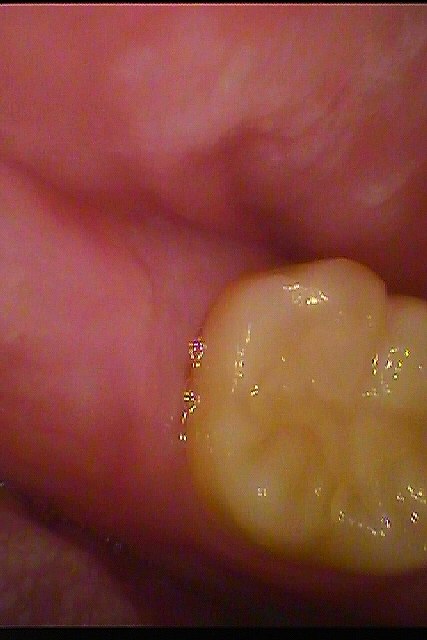

左下奥の完全埋伏歯の難抜歯 時々腫れる 近くの歯医者にて抜歯を行った方がよいといわれた|お知らせ |広島市安佐南区の歯科医院 左下奥の完全埋伏歯の難抜歯 時々腫れる 近くの歯医者にて抜歯を行った方がよいといわれた トップ お知らせ・ブログ お知らせ 左下奥の完全埋伏歯の難抜歯 時々腫れる 近くの歯医者にて抜歯を行った方がよいといわれた 左下奥の完全埋伏歯の難抜歯 時々腫れる 近くの歯医者にて抜歯を行った方がよいといわれた 問題の歯は見えません ここに親知らずが埋まっています パノラマになります 最小限で開けていきました 歯冠部を分割抜歯を行っていきました 根部を取りでしていきます 縫合して終了となります 綺麗に抜歯できました Web診療予約 初めての方へ 選ばれ続ける理由 院内設備について 歯が痛いしみる一般歯科 歯がぐらぐらする歯周病 健康な歯を保ちたい予防歯科 子供の虫歯予防をしたい小児歯科 銀歯をセラミックに審美歯科 白い歯を目指しませんか?ホワイトニング 矯正専門医がいるので安心矯正歯科 抜けた歯を補いたいインプラント・入れ歯 医院案内 スタッフ紹介 メリィハウス歯科クリニックオフィシャルホームページ ラベンダー歯科クリニックオフィシャルホームページ お知らせ・ブログ ホーム 診療科目 一般歯科 歯周病治療 予防治療 小児歯科 審美治療 ホワイトニング 矯正歯科 入れ歯・インプラント マウスピース矯正 初めての方へ 院長・スタッフ 設備紹介 医院案内・アクセス メニューを閉じる